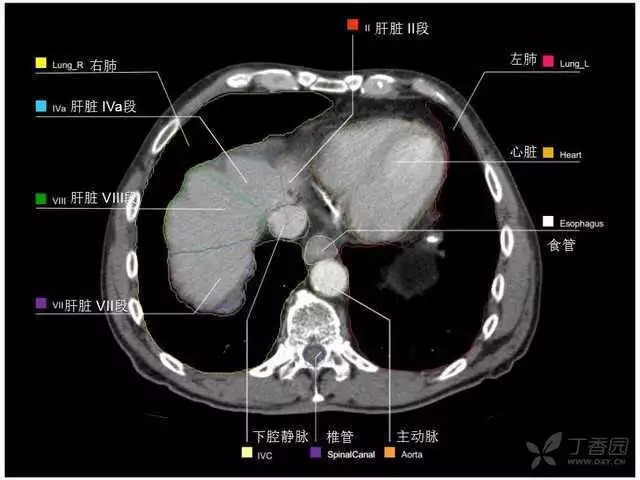

腹部肝脏高清CT断层的图谱

全腹部高清CT图谱,淋巴结彩色图谱,血管解剖图谱大汇总!

超声肝脏分叶及分段

肝脏分段和基本解剖学标志